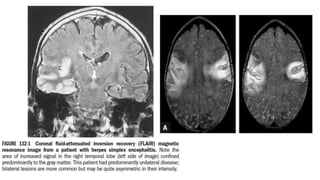

MRI, CT, and EEG

• Identify or exclude alternative diagnoses and differentiation between a

focal or diffuse.

• Focal findings - raises possibility of HSV encephalitis.

• Examples of focal findings include:

• MRI (T2; FLAIR, DWI) --- areas of increased signal intensity in the frontotemporal,

cingulate, or insular regions of the brain;

• CECT - focal areas of low absorption, mass effect; or

• EEG - periodic focal temporal lobe spikes on a background of slow or low-amplitude

(“flattened”) activity.

• PCR documented HSV encephalitis

• 80% will have abnormalities in the temporal lobe, and an additional 10% in

extratemporal regions.

• CT is less sensitive than MRI

• normal in up to 20–35% of patients.

• EEG abnormalities >75% of PCR-documented HSV encephalitis (2/3);

• typically involve the temporal lobes but are often nonspecific.

• a distinctive EEG pattern consisting of periodic, stereotyped, sharp-and-slow

complexes originating in one or both temporal lobes and repeating at regular

intervals of 2–3 s.

• between days 2 and 15 of the illness